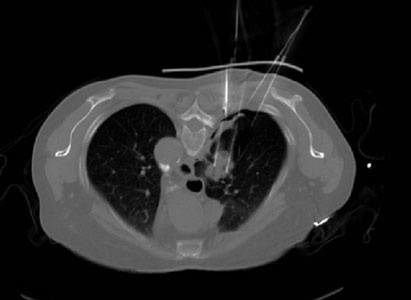

第三步,医生在扫描CT确认模板位置无误后,在模板预设针道上穿刺。(图3)

(图3)穿刺到预设深度后再次扫描CT